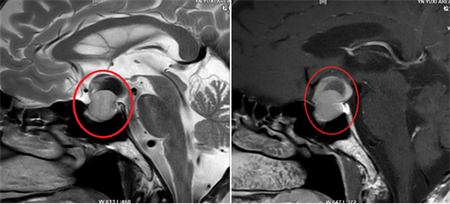

这次接受手术的是一位57岁的男性患者,因反复头晕有2月余来院就诊,经过磁共振检查后发现鞍区占位,临床考虑是垂体瘤。

神外一科对该患者的实际病情进行了充分的术前分析和讨论,在与患者和家属意见一致的情况下,决定为患者实施“全内镜下行经鼻蝶垂体瘤切除术”。手术由神外一科顾伟红和王超两位医师配合进行,手术开展非常成功,患者后期康复顺利,恢复良好。